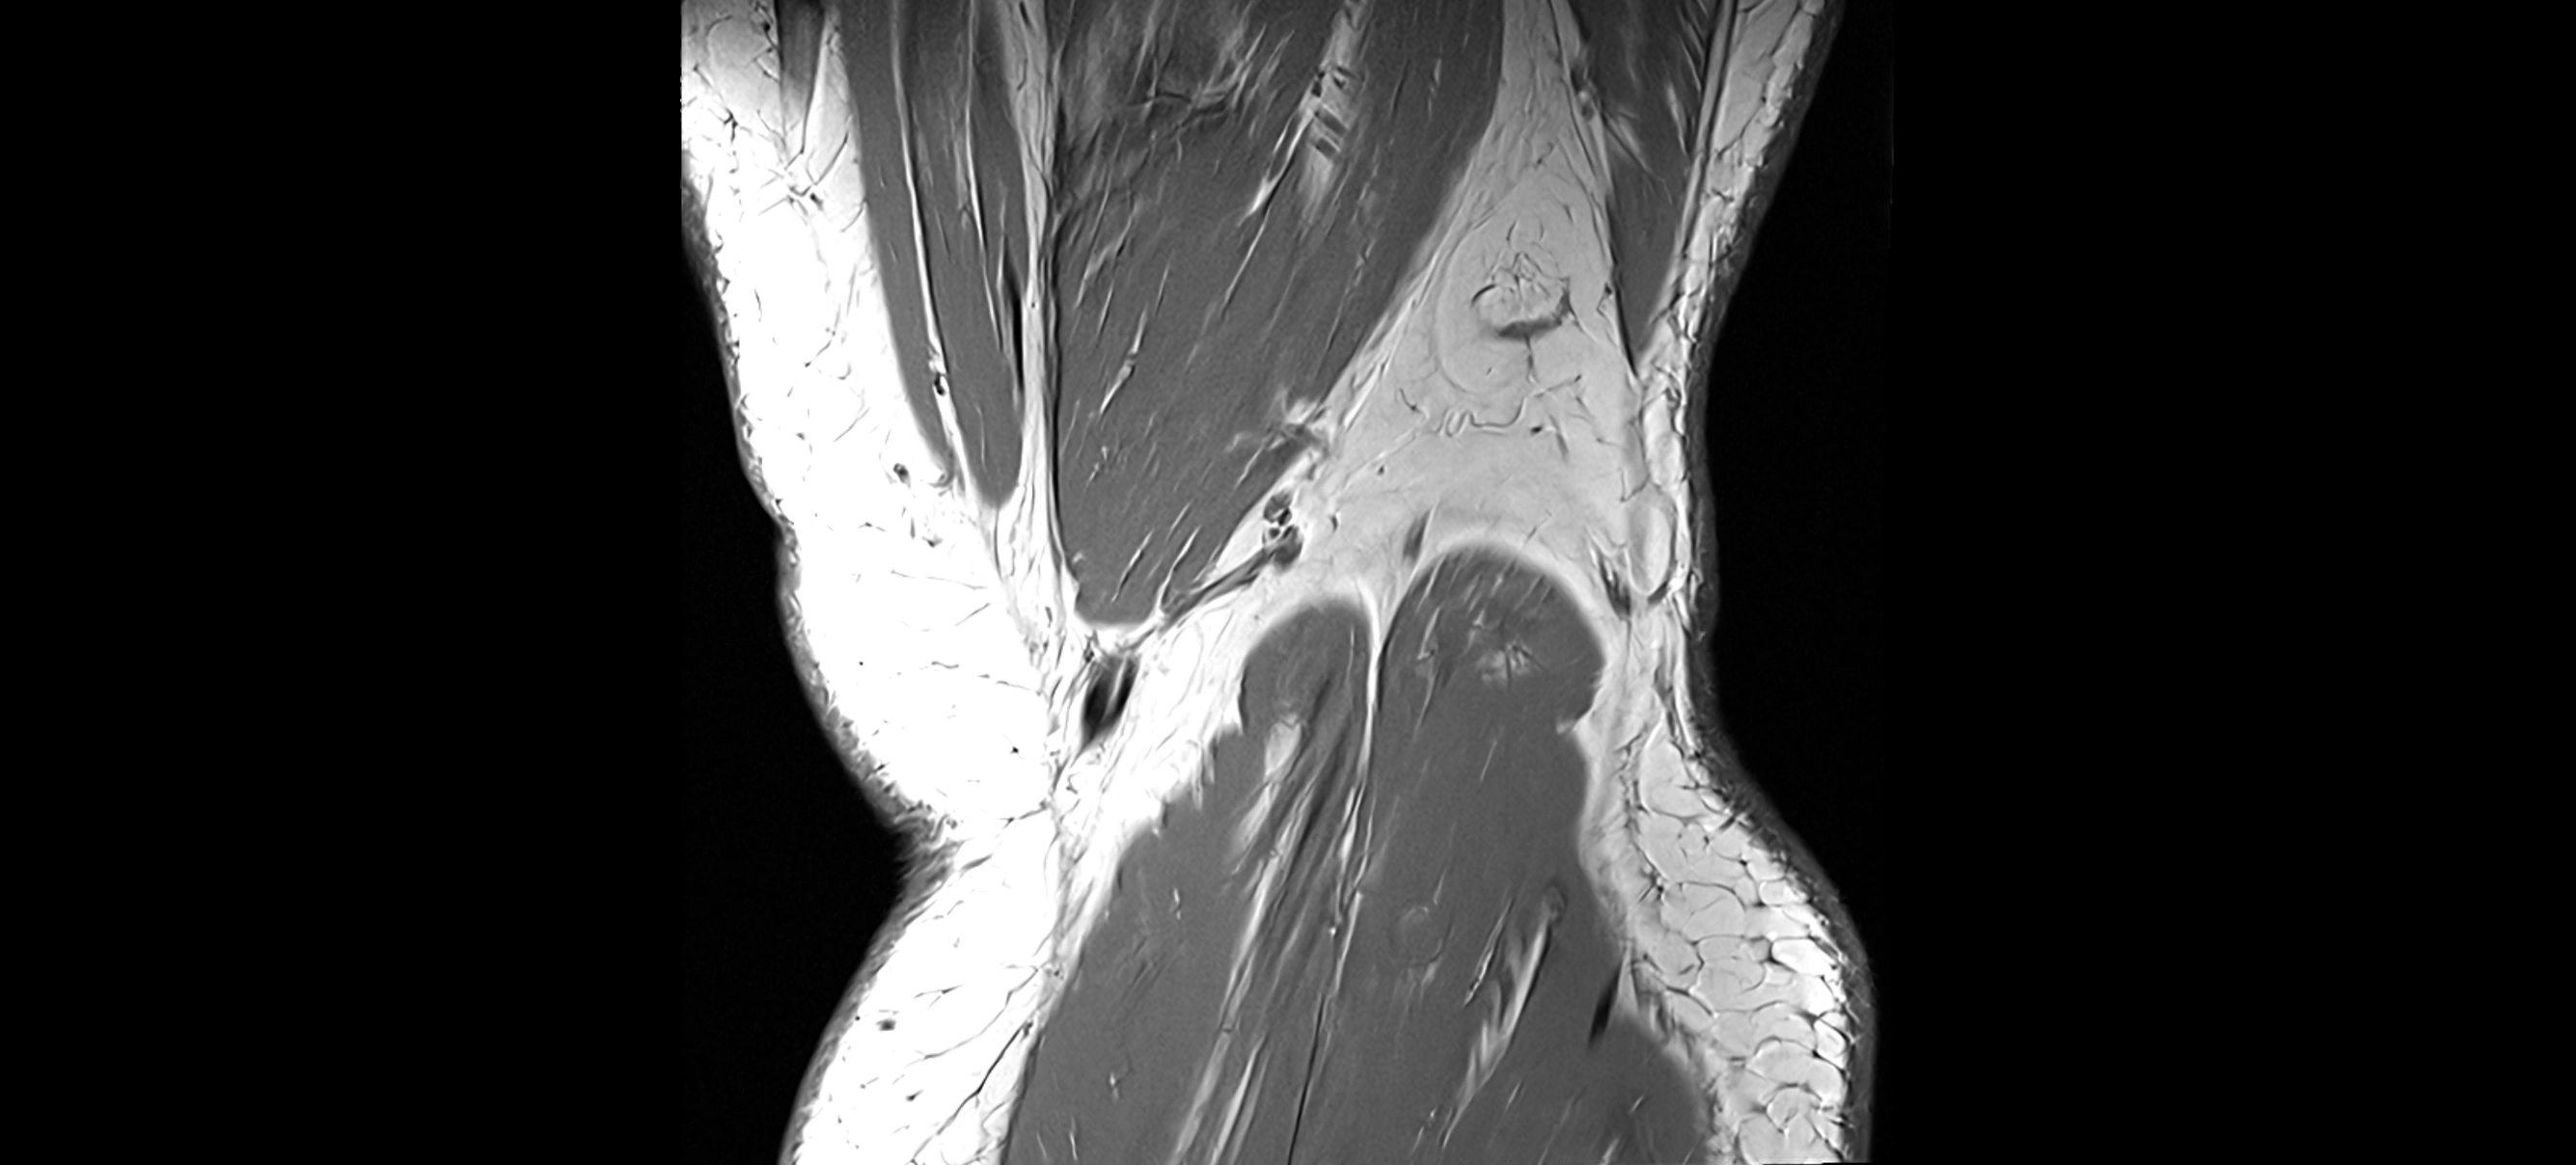

MRI Appearance

T1-weighted images:

• Normal ACL appears as a low-signal band-like structure crossing the intercondylar notch

• Surrounded by intermediate signal synovial fluid and fat planes

T2-weighted images:

• Normal ACL remains low signal

• Partial or complete tears appear as discontinuity, increased signal, or fiber laxity

MRI images

image